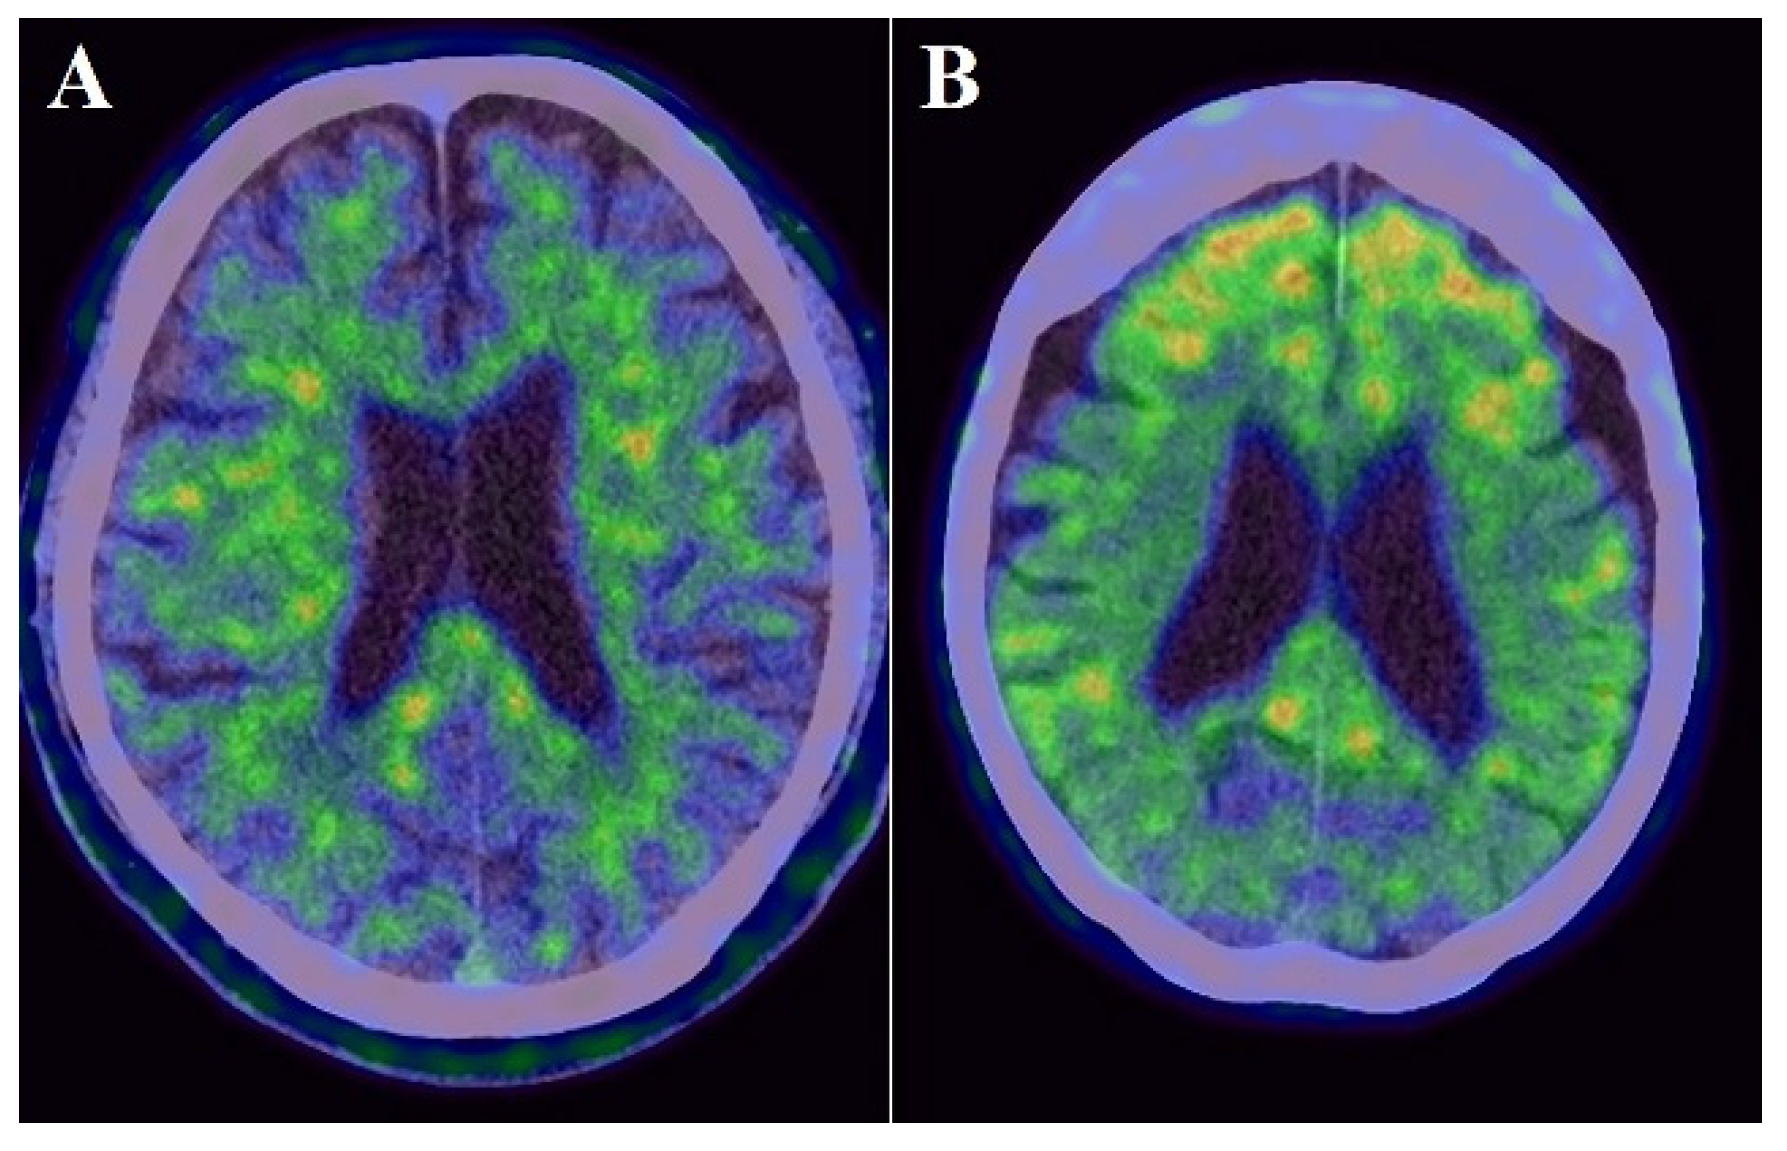

Figure 3.

Examples images of an individual with lower FDG uptake ((A): cortical SUVR value = 0.709) and with higher FDG uptake ((B): cortical SUVR value = 0.874).